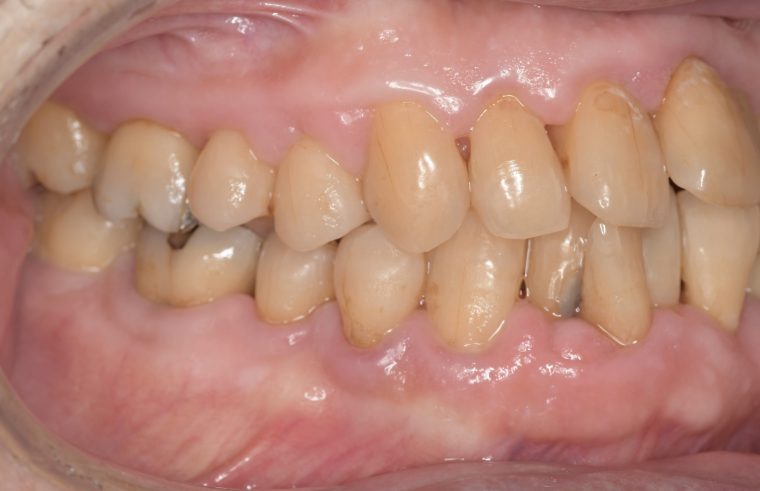

クリーニングの症例

現在の治療費と異なる場合がございます。最新の治療費は料金表をご確認ください。CASE 1

Before

After

基本情報

| 主訴 | 見た目をきれいにしたい |

| 治療期間 | 6ヶ月 |

| 治療費 | ジルコニアボンド(セラミックの被せもの)¥165,000×7(税込み) オフィスホワイトニング4回 ¥4,400×4(税込み) ホームホワイトニング¥11,000 |

| リスク・副作用 | かみ合わせがとても強い方の場合、稀に割れてしまうことがあります。 |

| 先生からの提案 | 上の前歯6本と右下の2番目の歯はセラミックの被せもので治療。 残りの下の前歯5本はプラスチックの材料で虫歯を治療し、 ホワイトニングをおこないました。白くなったご自身の歯の色に合わせてセラミックの 被せものを作成しています。 模型上で完成後をシュミレーションし、上の歯茎の位置をきれいに見えるように 揃えています。(外科処置はしていません) |